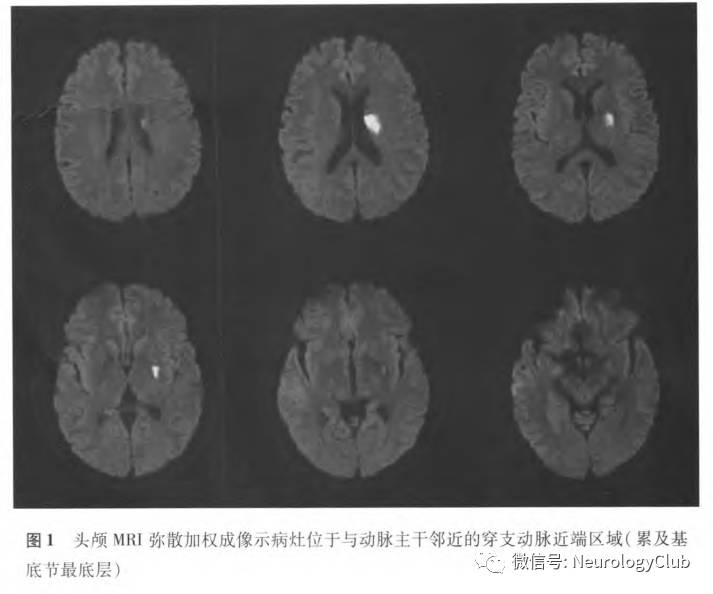

2. 临床诊断:目前临床上主要是通过MRI DWI上梗死灶与载体动脉的位置关系来确定(图1)。不同研究所采用的定义尚不统一。Yamamoto等将BAD定义为DWI上累及基底节区3个或以上层面且直径大于10mm的孤立梗死灶。Nakase等将BAD定义为DWI上累及基底节区3个或以上层面且直径>15mm的孤立梗死灶。Jeong等将BAD定义为在层厚为5mm的头颅MRI检测中,病灶在DWI上累及基底节区4个层面。Nah等将大脑中动脉供血区BAD定义为梗死灶累及基底节的最底部,且梗死灶大小限定为≤20mm。关于基底动脉穿支动脉疾病的定义比较明确(图2):在脑桥旁正中动脉供血区,梗死病灶在头部轴位DWI上由脑桥深部延伸至脑桥腹侧表面